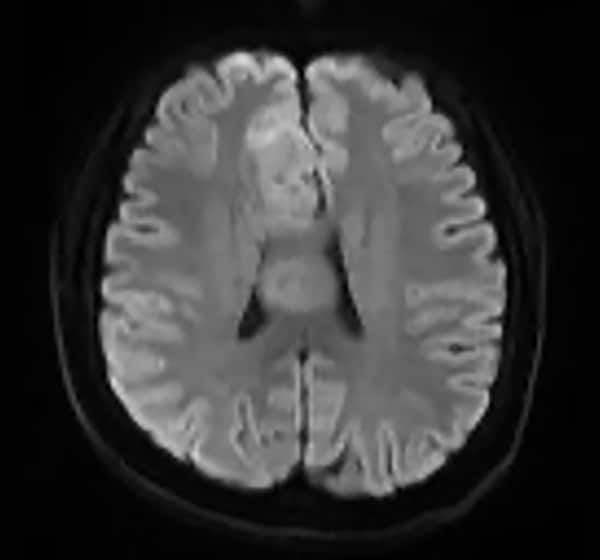

T1WI低信号、T2WI高信号、FLAIR高信号、DWIでやや高信号の腫瘤。Gdで腫瘤は造影されず、DSC-Perfusionでは辺縁~中心部に一部血流の高い部分あり。MRスペクトロスコピーではCho上昇とNAA低下がみられる。Low grade gliomaを疑う。後日、摘出手術が施行され、病理診断はoligodendroglioma NOS(Grade 2)であった。